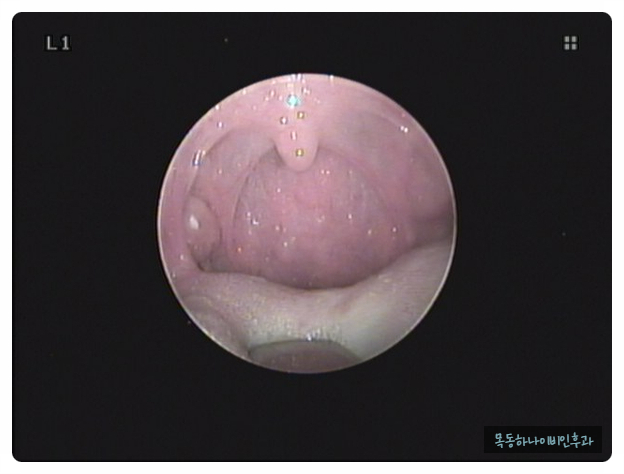

편도결석은 눈으로 확인하면 바로 진단이 가능합니다. 양치질이나 기침을 할 때 튀어나오거나 눈에 보이는 경우도 있습니다. 증상은 있지만 눈으로 관찰되지 않을 때 병원에서 후두 내시경으로 목 안쪽에서 관찰될 수도 있습니다.